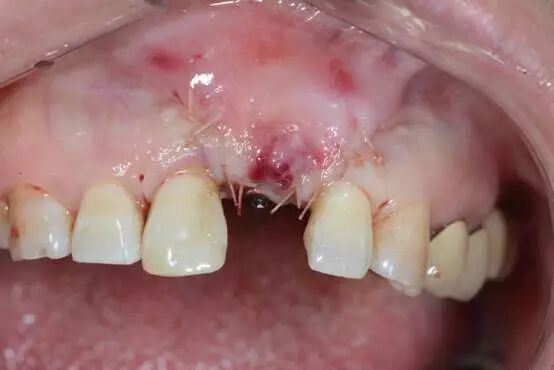

術(shù)后四周? 顎側(cè)

唇側(cè)

cription-url="https://mmbiz.qpic.cn/mmbiz_jpg/bW4QicIicGiabpPjCvbP0qtjXpOnJ4TDicN0kfI1VGUmGuCTzlicdQzag9tcDUUmaRicFBqO6iciakiaV6RF2JpficJWtIgA/0?wx_fmt=jpeg" data-backw="538" data-backh="457"/>